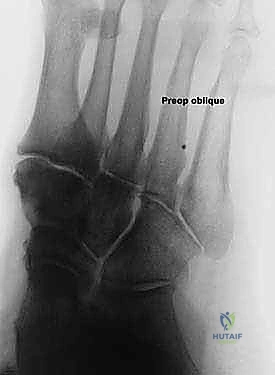

التصوير الشعاعي:

* الأشعة السينية (X-rays) مع تحمل الوزن: ضرورية لتقييم درجة انهيار القوس وزوايا العظام (مثل زاوية تالونافيكولار Meary's Angle).